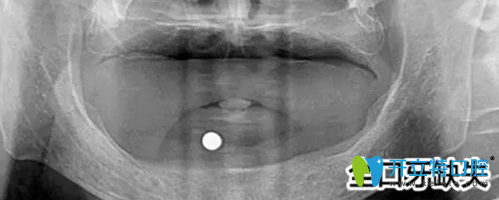

之后萬院長給郭先生做了詳細(xì)的檢查,首先給郭先生做了口腔全景片的檢查,發(fā)現(xiàn)郭先生前牙骨量不足,壁薄,需要植骨才能進(jìn)行種植牙手術(shù)。

郭先生的口腔全景片: